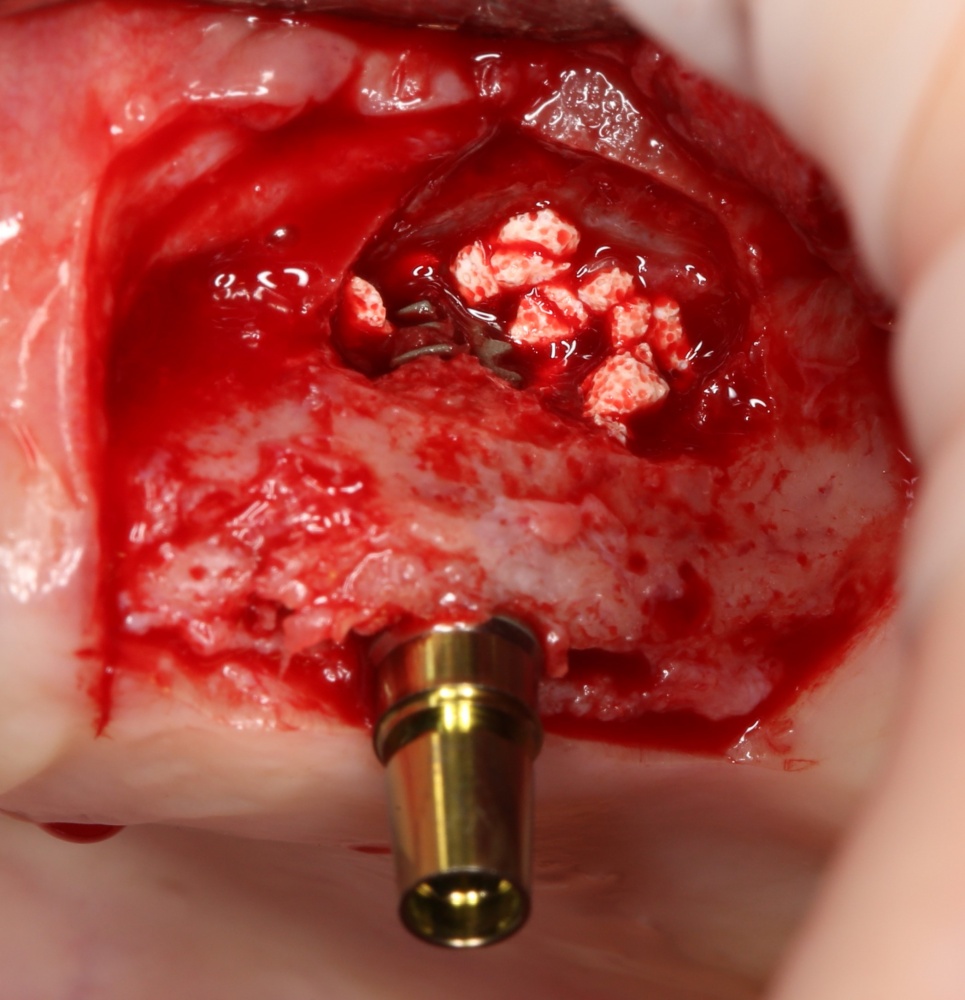

Для получения костного блока, мы открываем донорскую зону, наружную косую линию нижней челюсти.

Здесь потребуется пародонтологический зонд с миллиметровой разметкой или какой-то другой измерительный прибор (операционная линейка). Ранее по КЛКТ я измерил костный дефект, теперь нужно нанести границы будущего костного блока на донорскую зону.

Для получения костного блока мы использовали ультразвуковую пьезохирургическую систему. Это самый удобный и безопасный инструмент для проведения подобных манипуляций. С помощью него мы сформировали и выделили костный блок. Он должен отделяться легким движением остеотома или элеватора. Как это сделать правильно — читай здесь>>

Подготовка костного ложа и фиксация аутотрансплантата

Если ты читал мои предыдущие публикации, посвященные остеопластике, то наверняка знаешь, что костное ложе перед фиксацией графта (любого графта) требует некоторой подготовки. В основном она заключается в полном или частичном удалении кортикального слоя и, применительно к АТККФ — адаптации не только блока под ложе, но и ложа под пересаживаемый костный блок. Подробности здесь>>